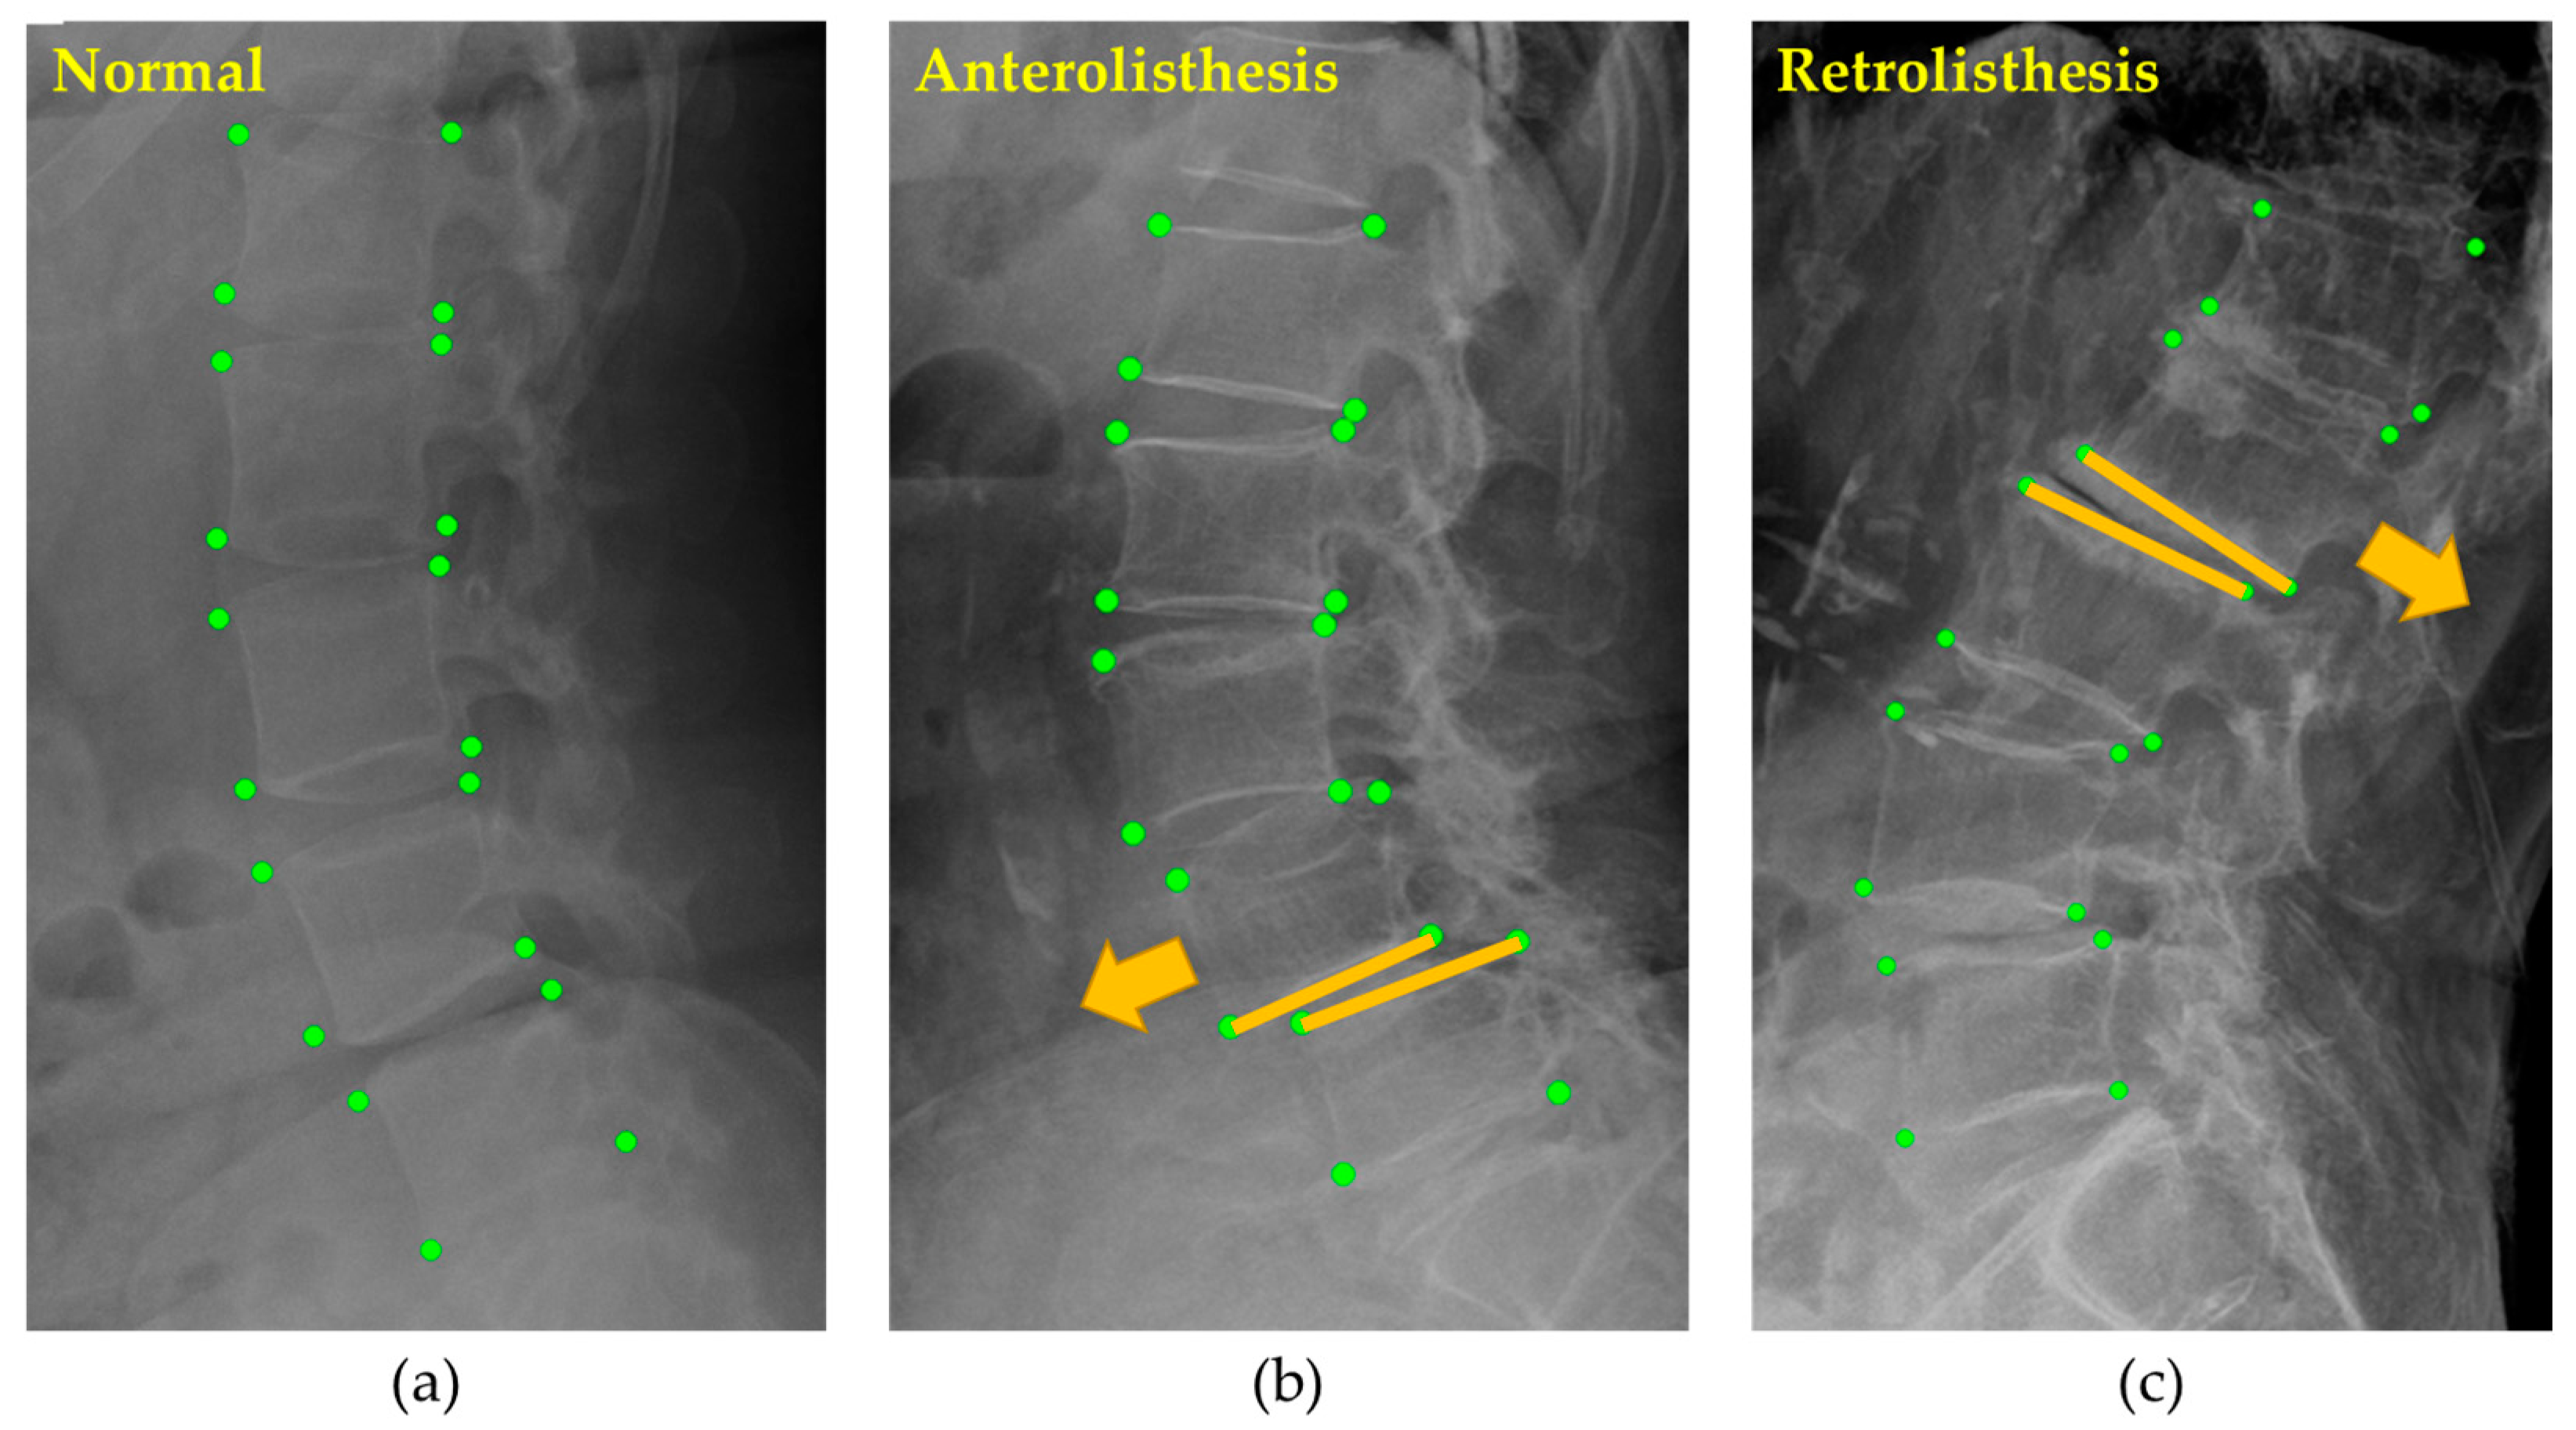

2.2.2. Spondylolisthesis